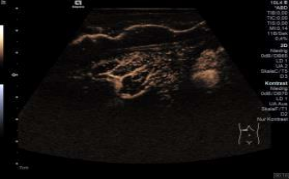

*超声造影增强能够提供实时的血管灌注的图像,这是CT/MRI不能提供的。

*造影成像保持最大峰值,对于低血流灌注的病灶或者在决定灌注的式上是非常有好处的。在一幅图像中,使用者可以通过控制“余辉”来控制时间用量。